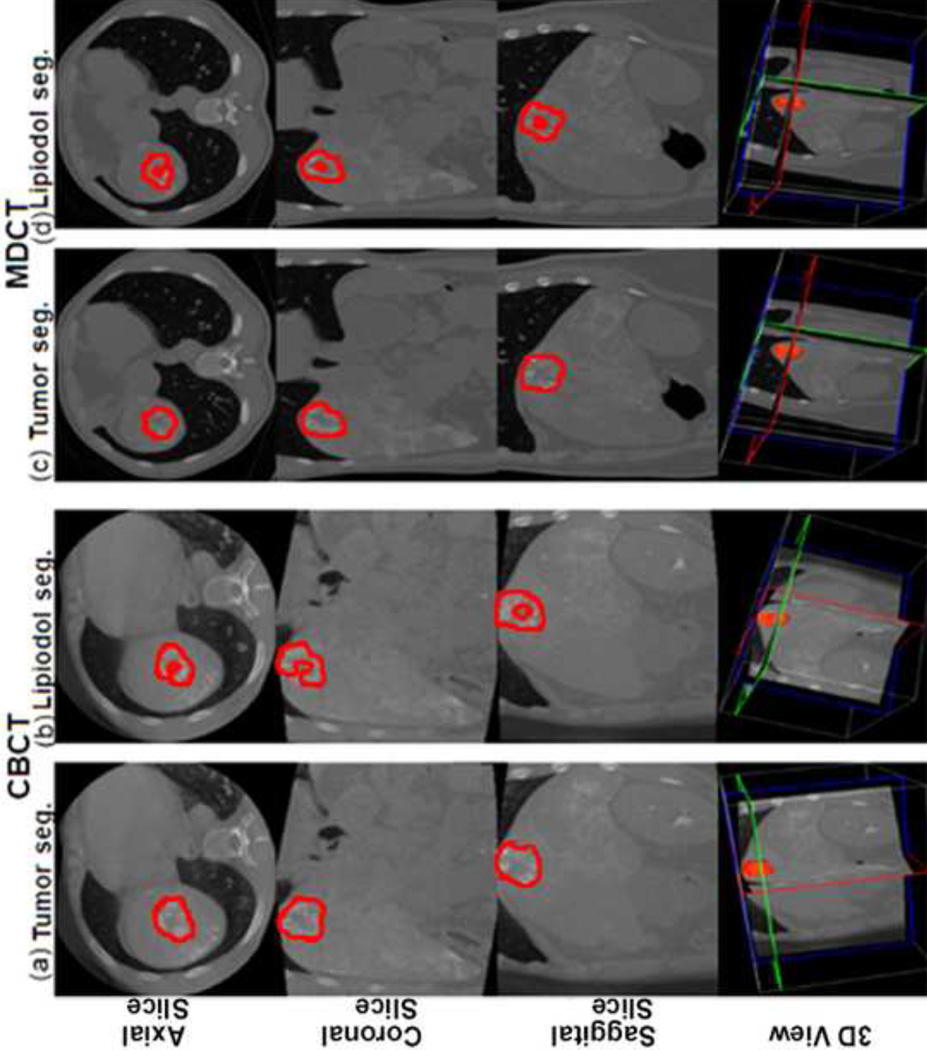

The volumes of the entire tumor and only the lipiodol retention on CBCT and MDCT were measured using the 3D segmentation software (Fig 2, Fig 3). As shown in Table 2, the average volume of the whole tumor and the lipiodol retention, and the calculated average percentage of lipiodol retention in the target tumors on CBCT were not significantly different when compared to MDCT. Additionally, the high correlation in both the tumor volume and the lipiodol volume between CBCT and MDCT imaging was evidenced by the linear regression analysis shown in Figure 2. The R2 value for the tumor volume and the lipiodol volume were 0.919 and 0.903 respectively (Fig 4), indicating the strong agreement between CBCT and MDCT.

Figure 3.

Tumor and lipiodol segmentation on CBCT and MDCT images in another patient case. (a) The tumor segmentation on CBCT images. Tumor volume=26.7cm3. (b) The lipiodol segmentation on CBCT images. Lipiodol volume=13.9cm3. The calculated percent of lipiodol retention on CBCT=52.1%. (c) The tumor segmentation on MDCT images. Tumor volume=32.8cm3. (d) The lipiodol segmentation on MDCT images. Lipiodol volume=13.7cm3. The percent of lipiodol retention on MDCT=41.8%.